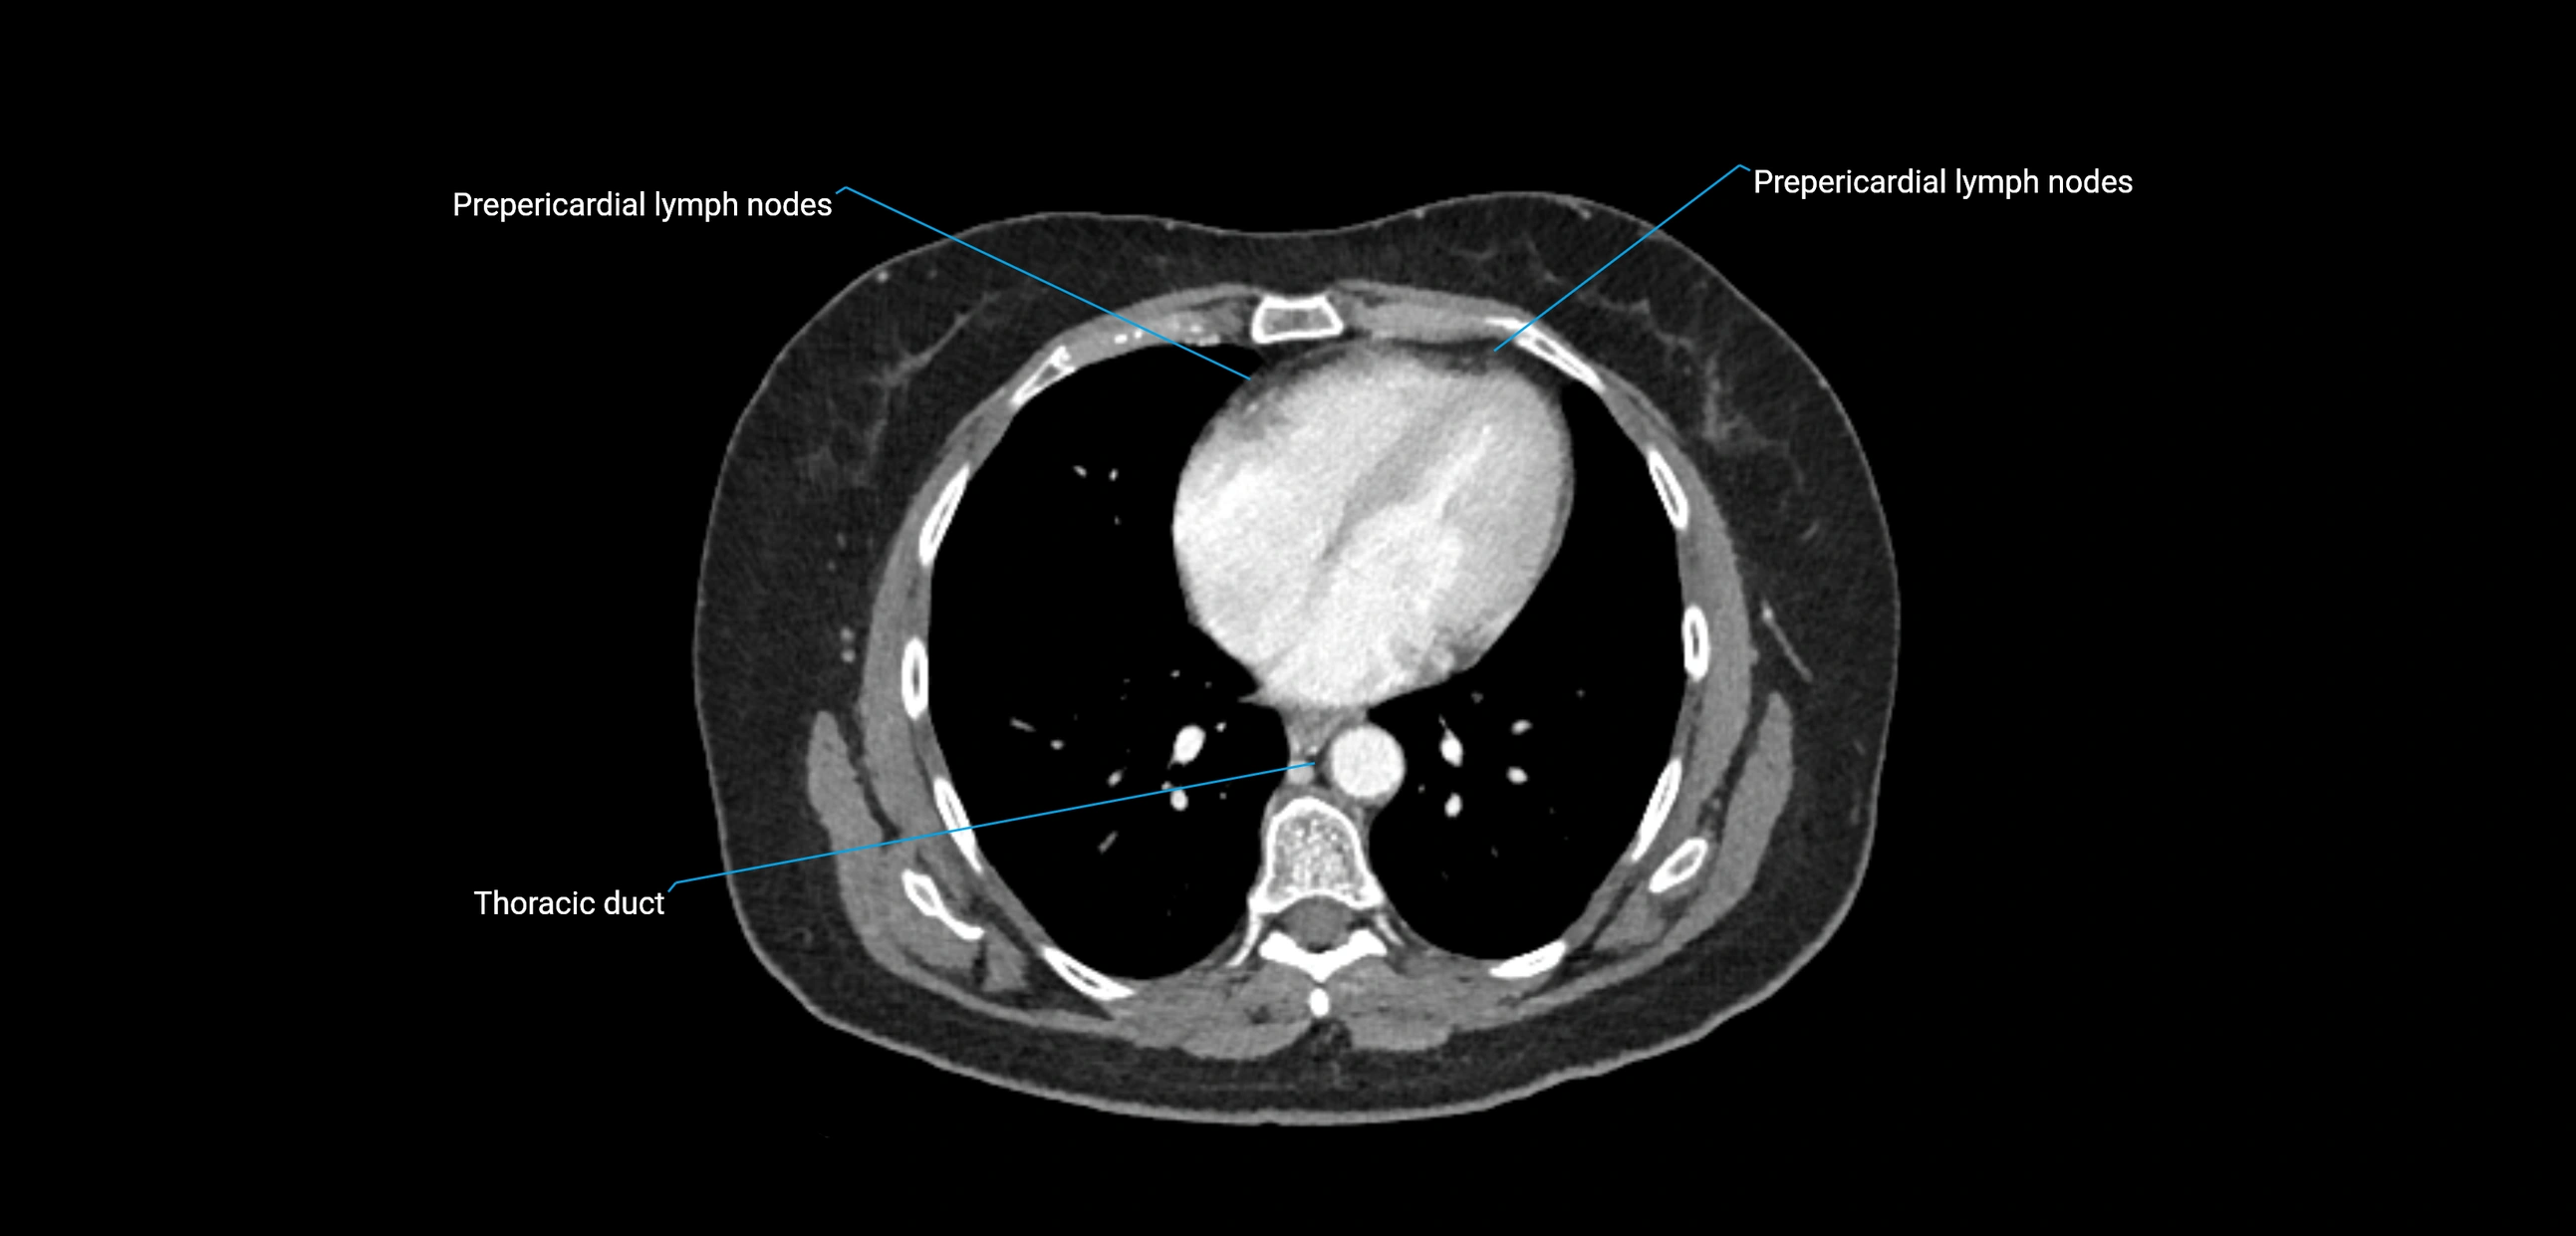

CT image

image